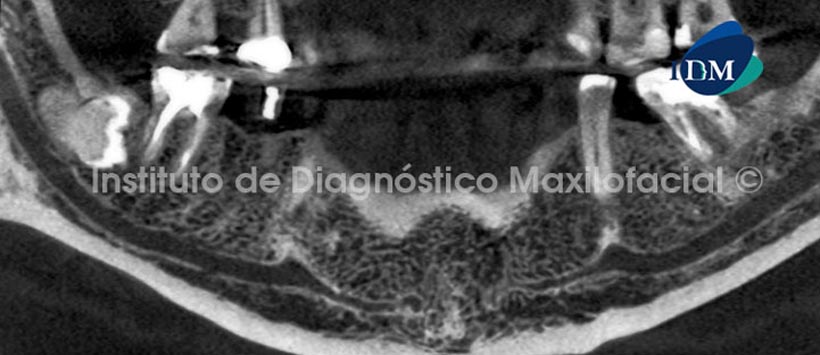

A la evaluación tomográfica se observa la proyección del conducto dentario inferior hacia la zona sinfisiaria, tal como se observa en la reconstrucción panorámica (Fig. 1), en la cual se relalizó un corte muy fino para la mejor visualización del conducto dentario inferior y del conducto incisivo mandibular.